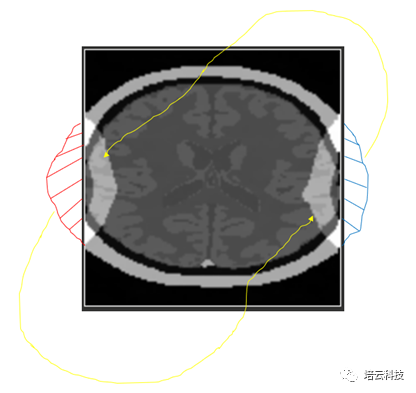

仔细观察会发现,其卷褶是对侧进行的(图4所示),即左侧溢出的部分会卷褶到右侧,而右侧溢出的部分卷褶到左侧。同理,上下侧卷褶也是同样的。那么为什么必须是对侧卷褶的?很欣慰有好学的学子线上提出这个值得深究的问题。

图4 卷褶伪影的对侧卷褶特点